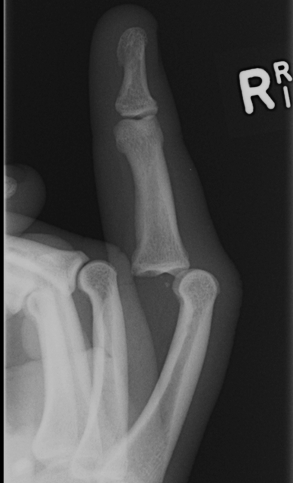

Volar PIPJ dislocations

A. Straight volar dislocation

Assessment of central slip post reduction critical

- if can active extend to within 30o, splint extended

- if nil active, surgical repair to prevent boutonniere

B. Volar rotary subluxation

- condyle button holes between central slip and lateral band

- irreducible dislocation

Lateral PIPJ dislocations

Rupture of one collateral ligament and volar plate

- may be bony avulsion

Management

- reduce and hold in extension 2/52, then protected ROM

- can perform primary repair or reconstruct